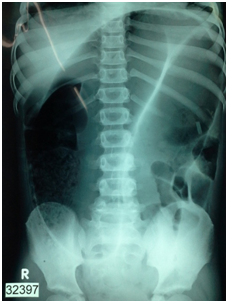

Routine blood investigations were performed and were unremarkable. The child was resuscitated with fluids and electrolytes and broad spectrum antibiotics were commenced. Abdominal Xay performed was suggestive of volvulus of the sigmoid colon i.e. Coffee bean sign (Figure 1). Sigmoidoscopic decompression was attempted but was unsuccessful, so it was decided to proceed with emergency laparotomy. Intra operative findings confirmed volvulus of the sigmoid colon with gangrene and impending perforation (Figure 2). Gangrenous segment of the sigmoid colon was resected (Figure 3). We decided against a primary anastomosis and performed a Hartmann’s procedure.

Figure 1 X-ray Abdomen showing the coffee bean or Omega sign.

In a large series reported by Smith,3 mean age of presentation was 8years. Predisposing factors were present only 33%. Abdominal pain (66%), vomiting (31%), were the commonest presenting symptoms while abdominal distention (69%), tenderness (41%) were the commonest signs. Similar findings were also reported from a Nigerian study.28 Recurrent lower abdominal pain with left lower abdominal tenderness has also been reported.8,10 These symptoms were noted in our patient also, although history of recurrent pain was not available. Although classic X ray appearance of coffee bean sign or omega sign was noted in our patient, this was not the norm for other series, with less than a third having this classic radiological sign, with Barium enema reported as having a higher diagnostic yield.3 Although common teaching is that” birds beak” appearance is path gnomic, Mellor et al reported that twisted appearance is more common and consistent with a diagnosis of sigmoid Volvulus.21 Not only is barium enema diagnostic, it can be therapeutic in uncomplicated cases though it might have to be repeated. In one large series 11 out of 14 colonic volvulus were successfully reduced with barium enema.21 Signs of impending perforation with peritonism are a contraindication to enema and mandates urgent surgical intervention as in the patient reported by us.